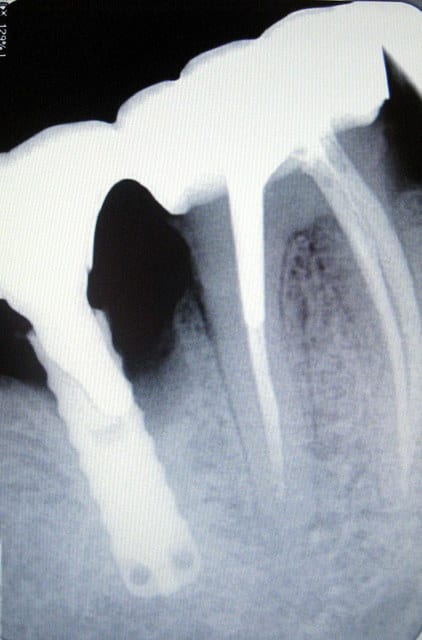

implant TBR lisse, des années 90, vis cassée, remplacée par un pivot "maison"...autres temps autres mœurs.

Le patient m'avait averti qu'il y avait eu du "sauvetage à la débrouille" sur ce vieil implant.;-)

Pas du tout le motif de la consultation du monsieur qui a 82 ans.

Le "bricolage" en question a été réalisé par un praticien tout à fait sérieux... qui n'avait pas lui-même posé l'implant.

J'ai vu le patient un peu rapidement en consult d'urgence et comme il avait des sensibilités partout, j'ai radiographié à tout va, et je dois dire que je n'ai pas été déçue.

Ceci dit, je me pose la question de l'ostéolyse en regard du tenon qui a été scellé dans l'implant. L'implant pourrait-il s'être fendu, surtout si on considère qu'il a été sollicité par le fait que le bridge est dento-implanto porté?

Il semble y avoir un reste de ciment en distal également ou autre chose d'un peu radio opaque, bon ça je vais nettoyer...